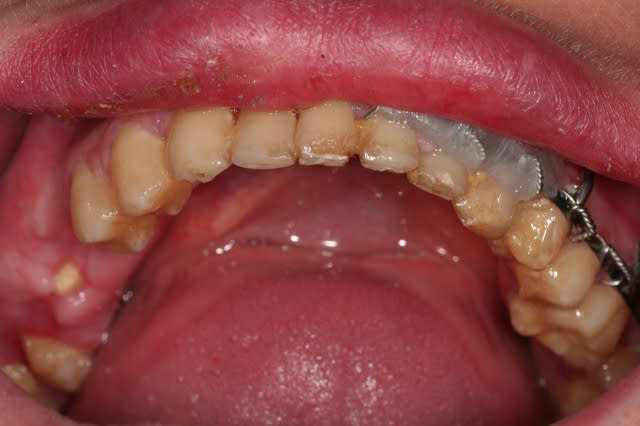

pas le temps de faire des commentaires ce matin, je balance le cas, et lâchez vous

C'est parce que je vois les PM cassées en biseau que je pense à un AVP, avec un choc d'impact sous le menton. Déjà eu ce cas mais pas si amoché quand même...

Parce que le reste du bloc antérieur ainsi que la 36 me semble bon pour la poubelle: lésions sur 11-21. 12?

donc, effectivement, un gros choc avec fractures multiples. effectivement marco, c'est un cas long mais qui n'a rien de sorcier en soi, je l'ai posté parce qu'il étendu et impressionnant.

pour l'instant j'en suis à concevoir une approche, et je bute sur 36 et 37: endo + élongation + ccm, ou alors extraction? je crois que la 36 va sauter, mais 37 m'embête.

Que prévois-tu pour les 4 incisives maxillaires?